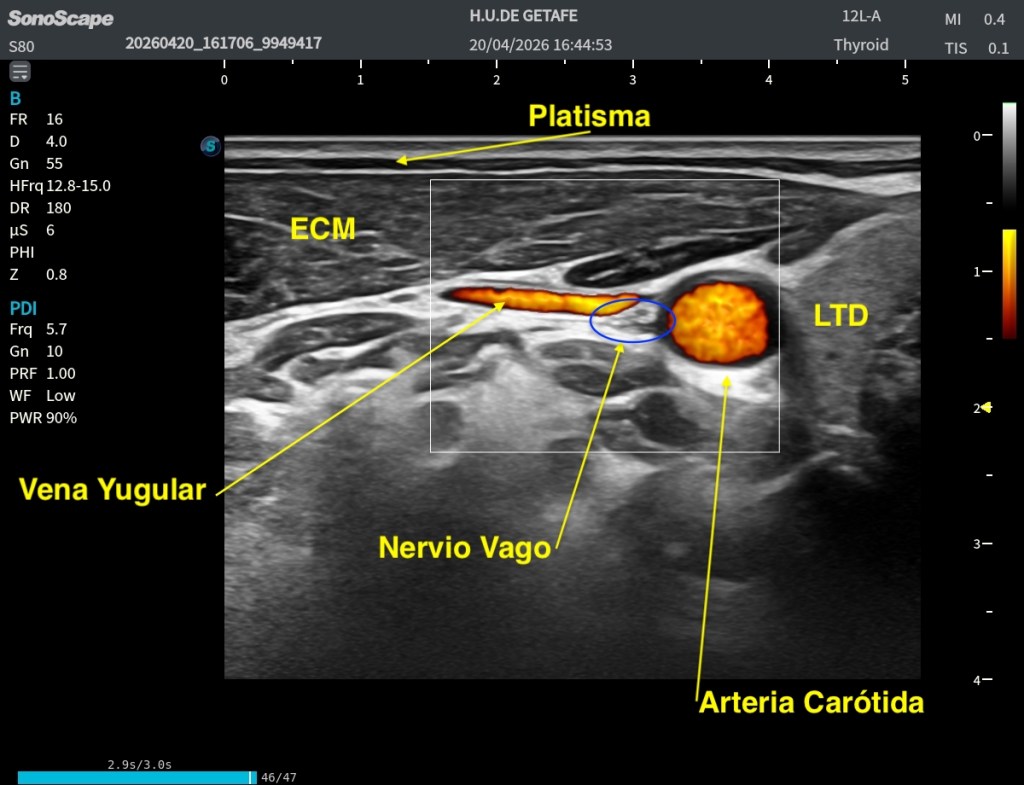

Desde el punto de vista anatómico, el nervio vago en el cuello discurre dentro de la vaina carotídea, acompañado por la arteria carótida y la vena yugular interna. Su localización más habitual es entre ambas estructuras, en un plano posterior. Es decir, se sitúa generalmente posterolateral respecto a la carótida y posteromedial respecto a la yugular interna. Es importante entender esto: no está adherido a una sola estructura, sino integrado en ese espacio anatómico común.

En ecografía, cuando trabajamos en eje corto y ya tenemos localizadas la carótida y la yugular, el nervio vago aparece como una estructura pequeña, de morfología ovalada o redondeada, difícil de ver si no lo buscas ya que es muy pequeño, milimétrico, igual te acabas de enterar de que se puede estudia…con un patrón fascicular típico. Presenta una alternancia de zonas hiperecogénicas e hipoecoicas, con ese aspecto característico que describimos como “gominola de mora”, habitualmente ligeramente achatada, tipica de ecoarquitectura de nervio.

La forma de explorarlo es sistemática y muy reproducible. Vamos a realizar un corte axial a nivel de la porción anterolateral del cuello. Ajustamos el ecógrafo con los parámetros con el preset cervical o tiroides y el transductor en esa posición antero lateral dirigiendo el haz hacia postero lateral del lado contrario, para poder identificar claramente tanto la vena yugular interna como la arteria carótida. Una vez localizadas ambas estructuras, debemos centrarnos en el espacio entre ellas. Es ahí donde, en la mayoría de los casos, va a aparecer esta estructura pequeña con patrón nervioso (dentro del óvalo azul en la imagen siguiente), que corresponde al nervio vago en su visualización en eje transversal o axial. Podemos usar la anatomía cervical global, para ubicarlo como aparece en la foto.